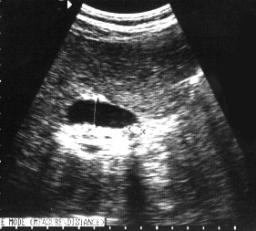

Descripción de las Imágenes:

En ésta imagen se observa el diafragma, derrame pleural y colección de líquido con tabiques múltiples a nivel subdiafragmático. La estructura hepática muestra un aumento de la ecogenicidad.

Colección líquido subfrénico tabicado. Derrame Pleural

Las colecciones subcapsulares de hígado y bazo son fácilmente identificables cuando se observan inferiores respecto al complejo ecogénico diafragmático unilaterales y adoptando la forma de la cápsula orgánica. Las colecciones hepáticas subcapsulares perrmanecen confinadas por el ligamento falciforme y, a diferencia del líquido intraperitoneal, pueden extenderse medialmente respecto al inserción del ligamento coronario superior. Con la respiración se da de forma característica una ausencia de variación en la colección subcapsular relativamente al órgano.-